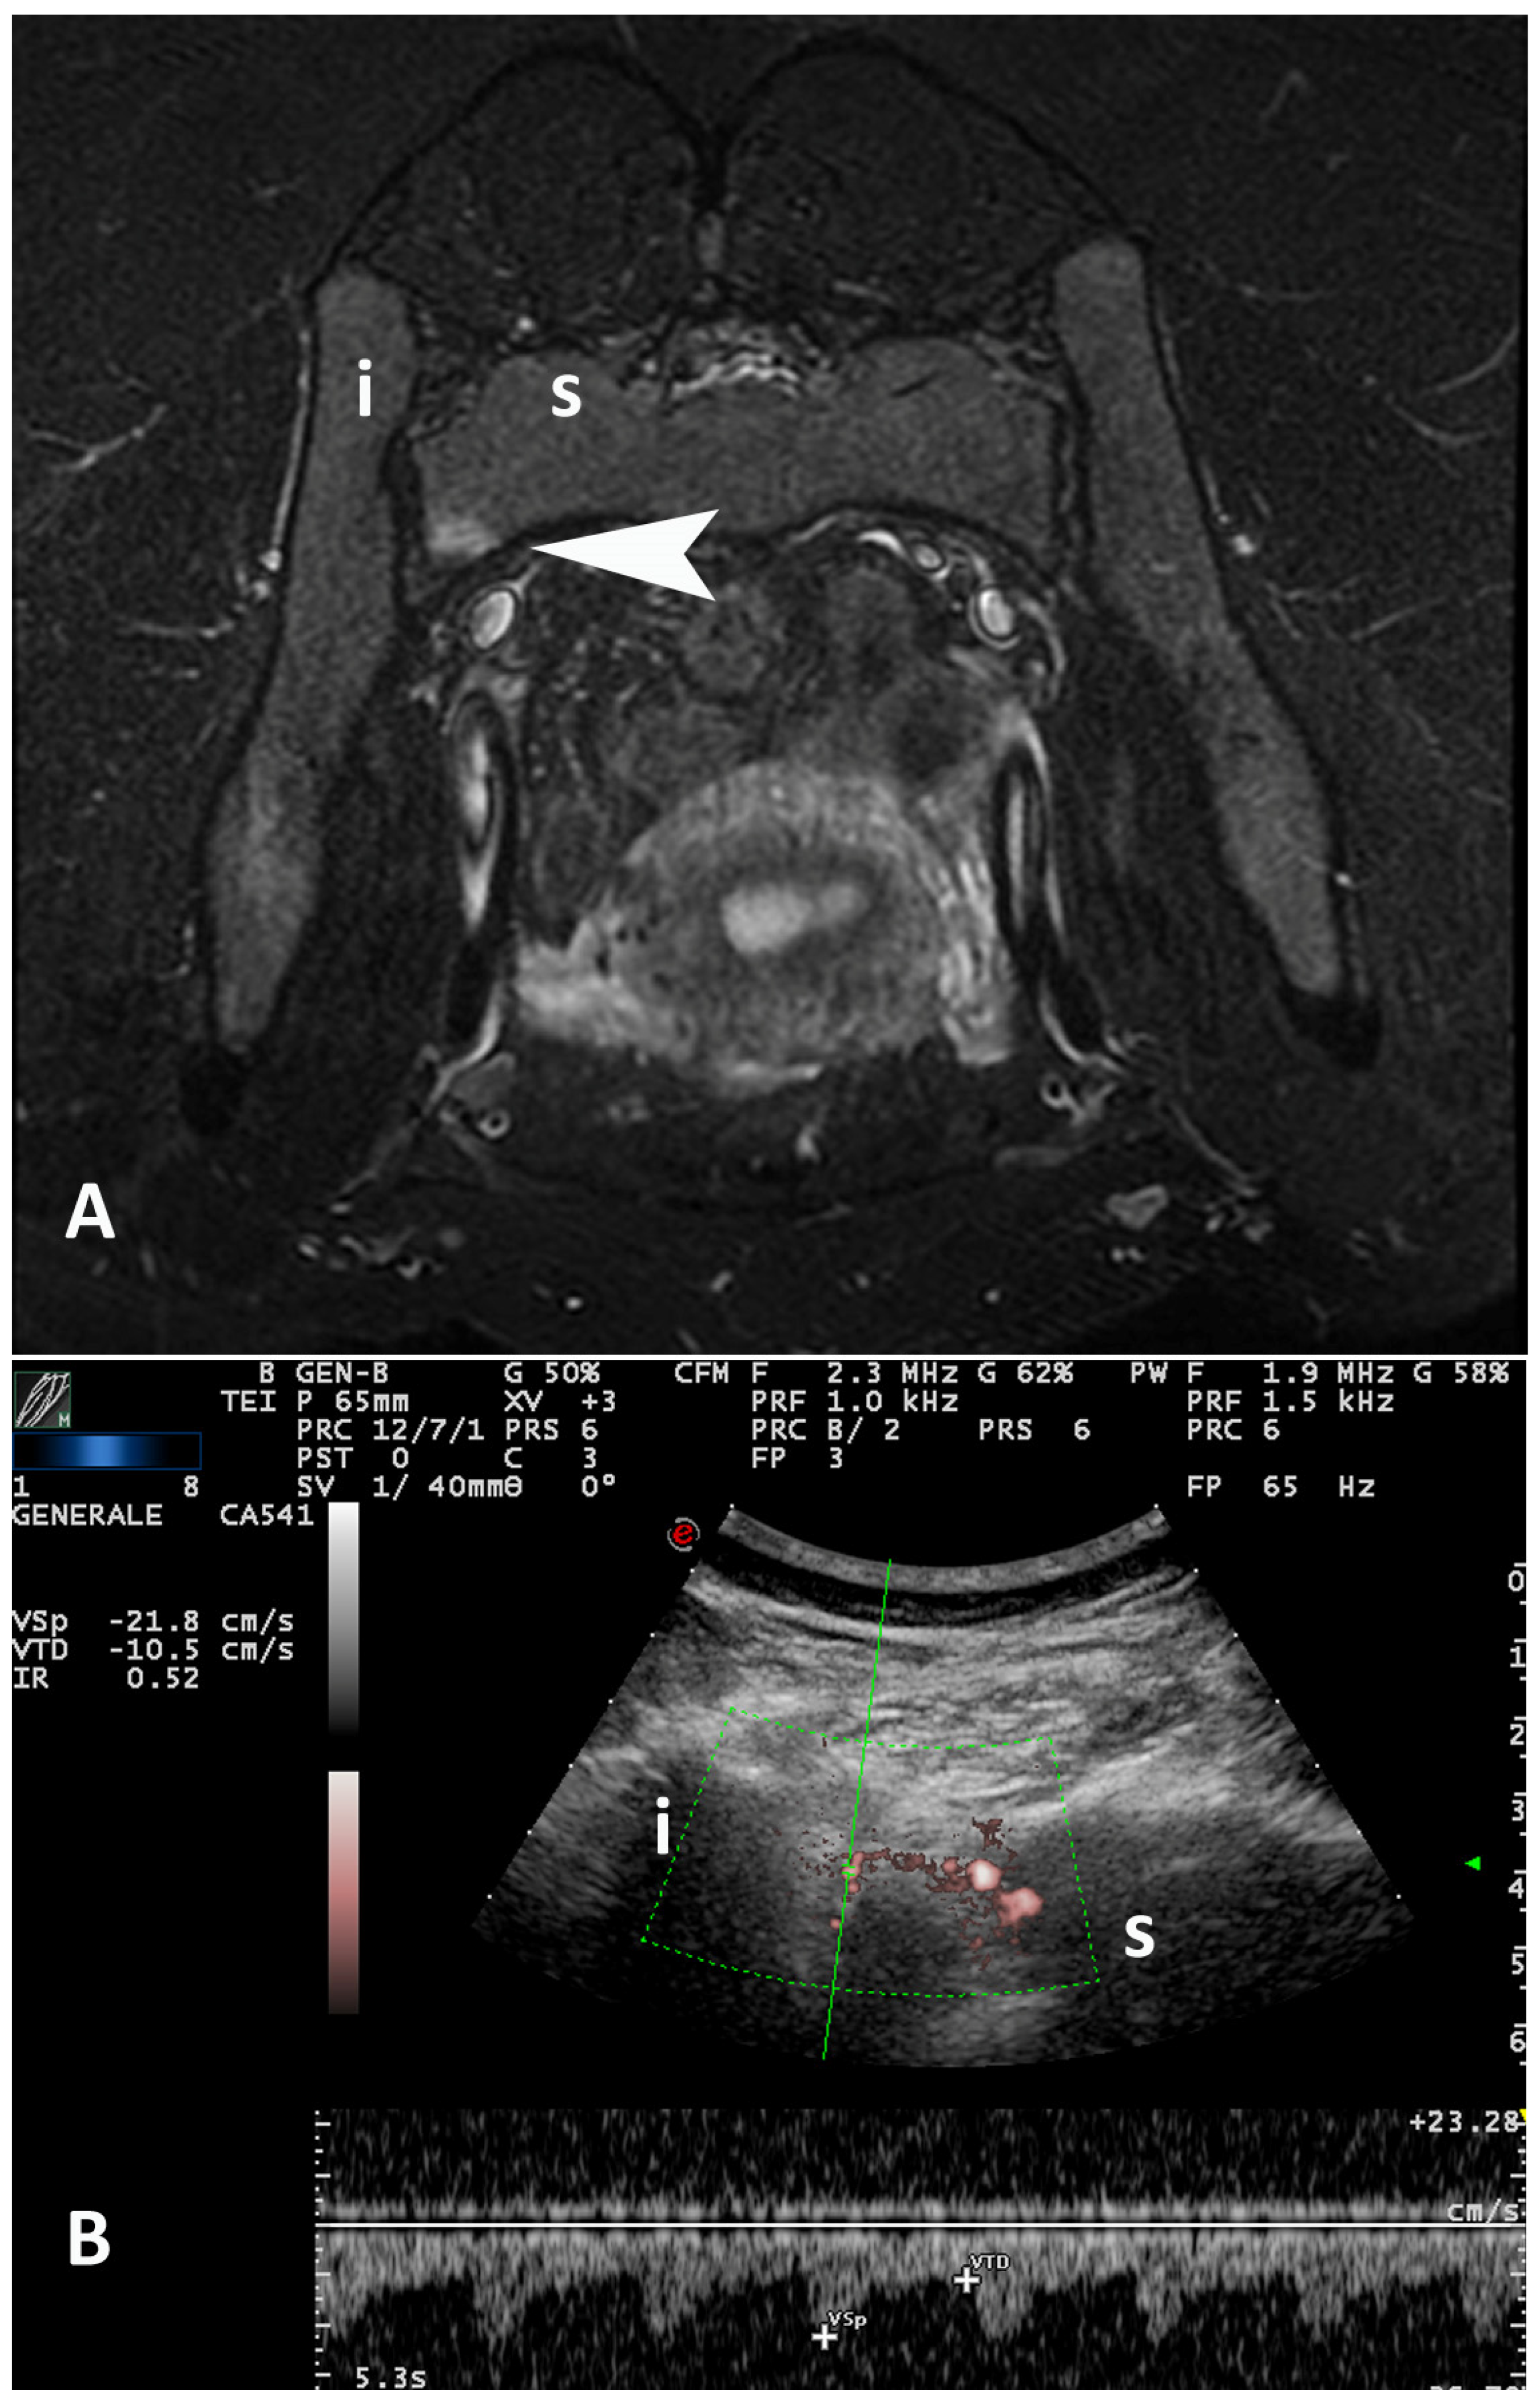

- Falsetti, P.; Conticini, E.; Mazzei, M.A.; Baldi, C.; Sota, J.; Bardelli, M.; Gentileschi, S.; D’Alessandro, R.; Al Khayyat, S.G.; Acciai, C.; et al. Power and spectral Doppler ultrasound in suspected active sacroiliitis: A comparison with magnetic resonance imaging as gold standard. Rheumatology 2021, 60, 1338–1345. [Google Scholar] [CrossRef]